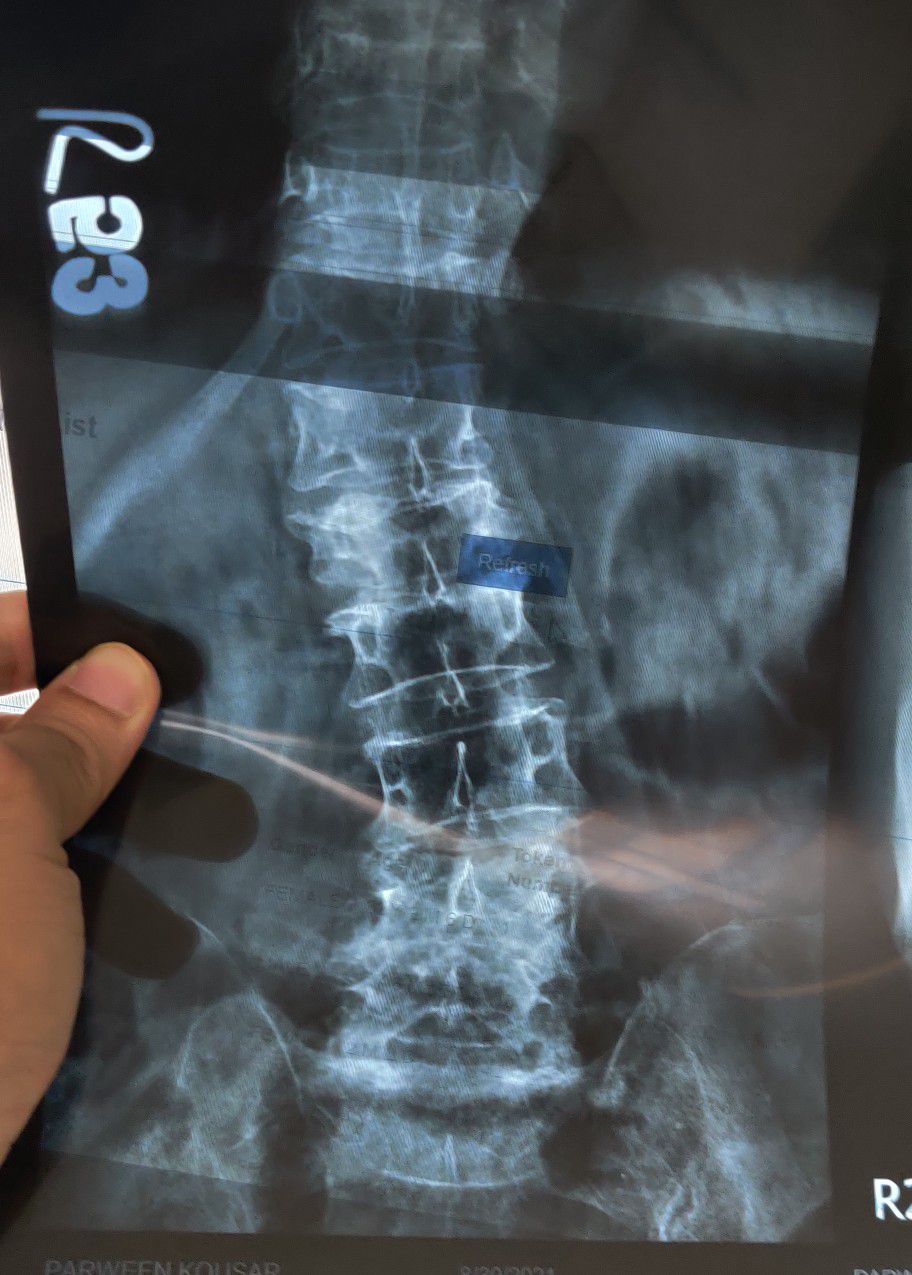

Scoliosis

Xray

Ortho